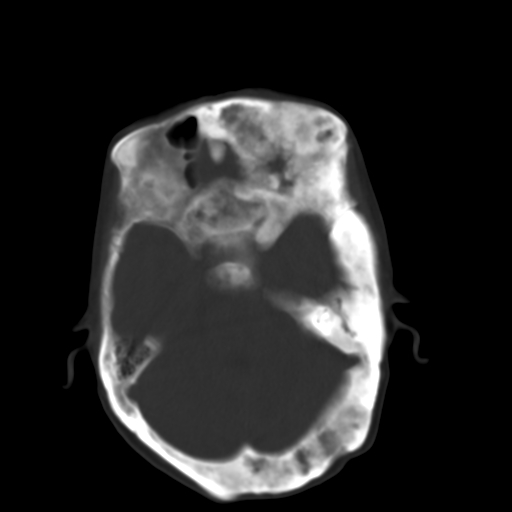

标题: CT17003:F58Y,骨纤维异常增殖征 [打印本页]

标题: CT17003:F58Y,骨纤维异常增殖征

女58y 头晕就诊

左侧额骨增厚,板障层密度增高。 支持骨纤维异常增殖症  。

符合颅骨骨纤维异常增殖症表现。